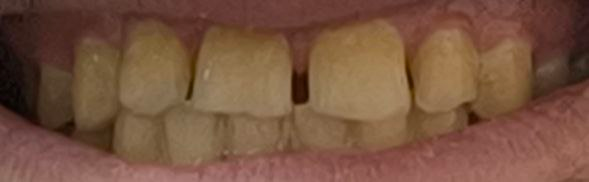

Аноним 25/07/25 Птн 15:53:49 1633255 15

изображение.png 897Кб, 800x601

привет двач, мне 24 года и меня заебал ебучий темно-коричневый межзубный налет, который появляется через месяц после профгигиены вне зависимости от прикладываемых усилий

прежде чем мне тут посоветуют купить зубную нить, опишу свою ежедневную рутину (ни один шаг в которой я никогда не скипаю, я серьезно)

утро:

1. зубная нить (та которая толстая и от воды расширяется), пользоваться умею

2. чистка зубов минимум 2 минуты электрической зубной щеткой, паста 75 рда с фтором папаином (написано расщепляет зубной налет, в душе не ебу правда или нет), чистить умею. раз в неделю гоняю на режиме отбеливания, тоже не ебу делает он что-то или нет, наверное нет

3. прохожусь монопучком по всем зубам с пастой еще раз

между приемами пищи пью дохуя воды

вечер:

1-3 шаги аналогично

+ гель для реминерализации

на последнюю чистку въебано 8 тысяч у какого-то распиздатого стоматолога, посоветовал мне как раз монопучок, ершики подобрал по размерам межзубных пространств, у меня поехала крыша и рутина месяц после чистки выглядела так:

1. зубная нить

2. зубная щетка с пастой

3. монопучок с пастой

4. ершики для межзубных пространств с пастой

в течение дня после КАЖДОГО приема пищи хуярю зубной ниткой и иногда дополнительно ершиком с пастой, ополаскиваюсь ополаскивателем

1-4 аналогично и гель для реминерализации

попробуйте угадать как выглядели мои зубы через месяц после этого? верно, точно так же в коричневом налете между зубами

я не бомж но у меня нет желания каждый месяц всирать по несколько тысяч на чистку

проблема существует по всей видимости с пиздючества

я пью с утра 2 чашки кофе (до чистки зубов), в течение дня еще чай пью зеленый, без этого не могу, но воды я один хуй больше пью

с 18 курю сиги, с 21 только вейп, но повторюсь проблема существует с пиздючества

кариесов у меня никогда не находят, все зубы здоровые, с прикусом все заебись после брекетов, воду водопроводную не пью и не знаю каким ебланом нужно быть чтобы ее пить в россии, но почему-то спрашивают иногда

желудок не беспокоит

сахара мало жру

хуй знает что еще написать

двач помоги пожалуйста, мне стыдно рот на людях открывать

пикрандом для привлечения внимания